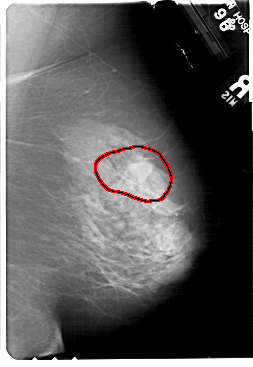

FILE: A_1720_1.RIGHT_MLO.OVERLAY

TOTAL_ABNORMALITIES 1

ABNORMALITY 1

LESION_TYPE MASS SHAPE ARCHITECTURAL_DISTORTION MARGINS SPICULATED

ASSESSMENT 4

SUBTLETY 2

PATHOLOGY MALIGNANT

TOTAL_OUTLINES 1

BOUNDARY